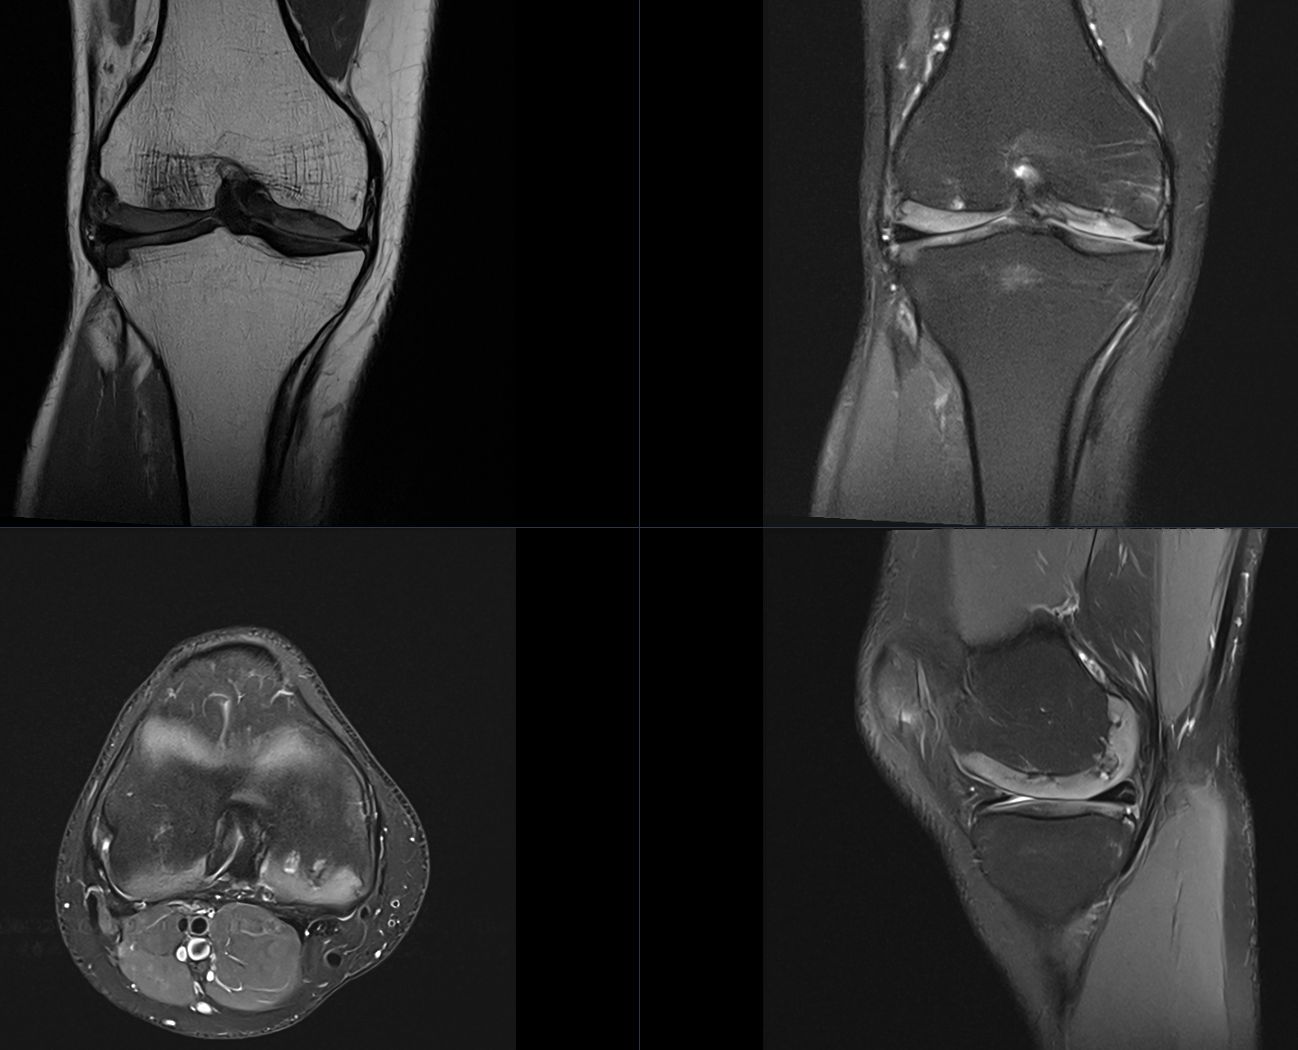

Dear colleagues, I’d appreciate your thoughts on a chronic knee pain case with MRI findings of thickened cartilage in the tibia and femur (suspected congenital), irregular signal changes with cystic alterations, and mild downward-facing medial/lateral tibial joint surfaces. ACL, PCL, collateral ligaments, quadriceps tendon, and patellar ligament: Normal. Minimal posterior degeneration in the medial meniscus.

![]()

Congenital Cartilage Thickening or Syndrome? Read More »